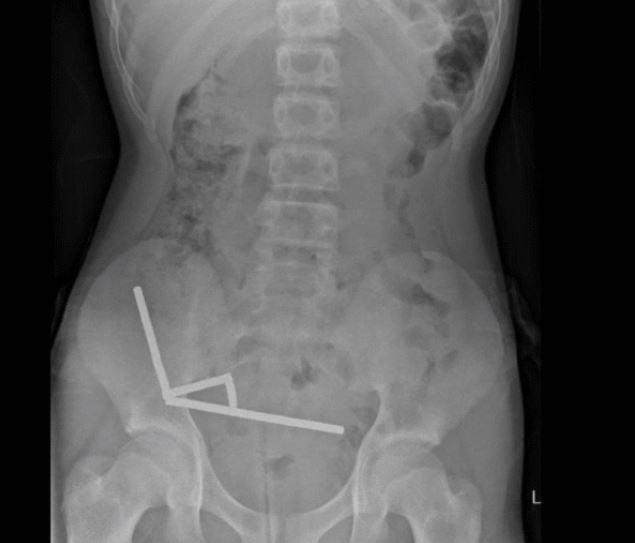

Αφορμή αποτελεί ένα σοβαρό περιστατικό στη Νέα Ζηλανδία όπου 13χρονος κατάπιε σχεδόν 200 μαγνήτες και εισήχθη στο νοσοκομείο με πολύ έντονους κοιλιακούς πόνους.

Όπως αναφέρει το New Zealand Medical Journal, οι μαγνήτες ενώθηκαν μεταξύ τους σε μια περιοχή που ενώνει το λεπτό και το παχύ έντερο και έγιναν αιτία να νεκρώσουν ιστοί λόγω έλλειψης αιμάτωσης. Ο 13χρονος υπεβλήθη σε επέμβαση και παρότι αναρρώνει καλά, έχασε μέρος του εντέρου του.